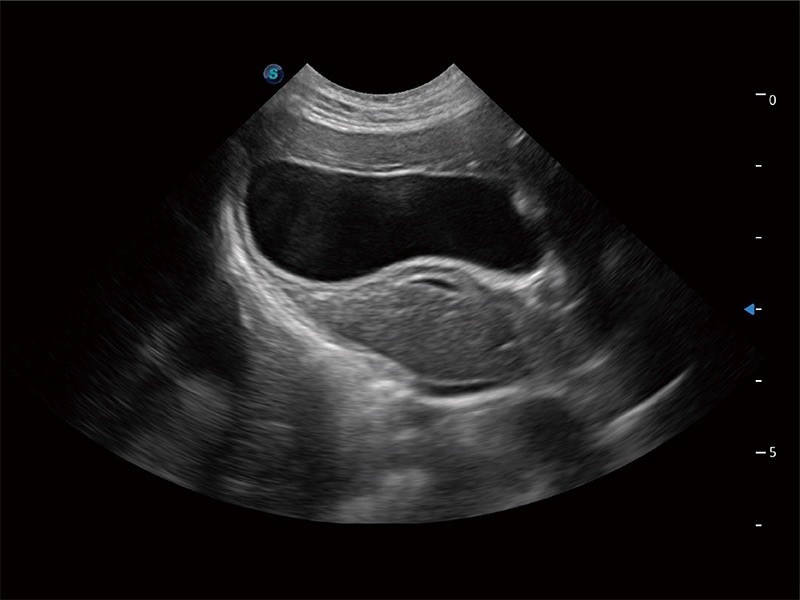

ProPet 80 配备了丰富的心脏探头群、先进的成像技术和专业的心脏测量工具,可帮助动物医生为不同体型和生理结构的动物提供心脏和心肌功能的全面评估。

实时用颜色表示心肌组织运动,观察和定量组织的运动情況,对快速检测与评估心肌的灌注和活性、电传导及心肌收缩和舒张功能等均能提供重要的诊断信息。